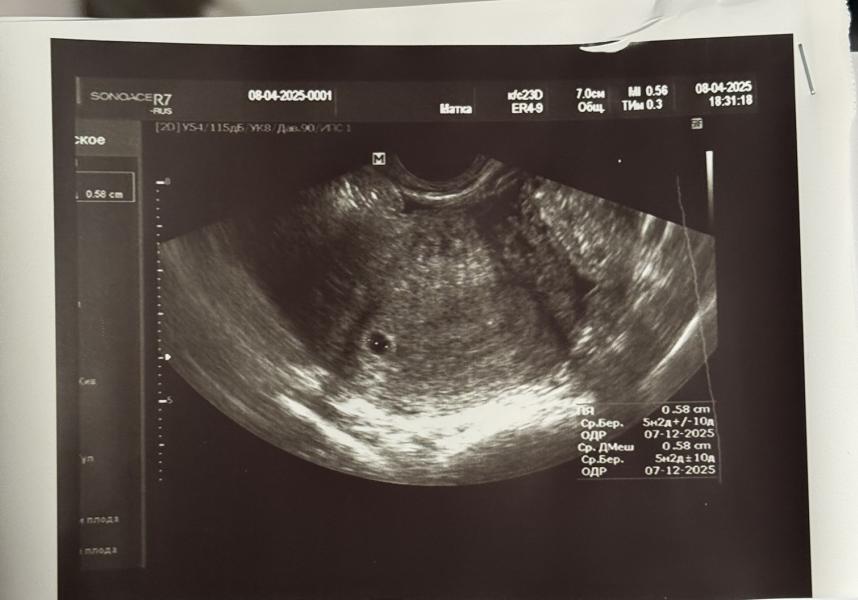

Первое УЗИ: долго искали плодное яйцо, переживала за внематочную, но все хорошо!

Сегодня было первое узи, почему то очень переживала на счет внематочной беременности, и как на зло долго не могли ПЯ найти, вот это я извелась за эти 5 минут😅 Но все хорошо, теперь я спокойно жду следующего узи через 2 недельки 🥰